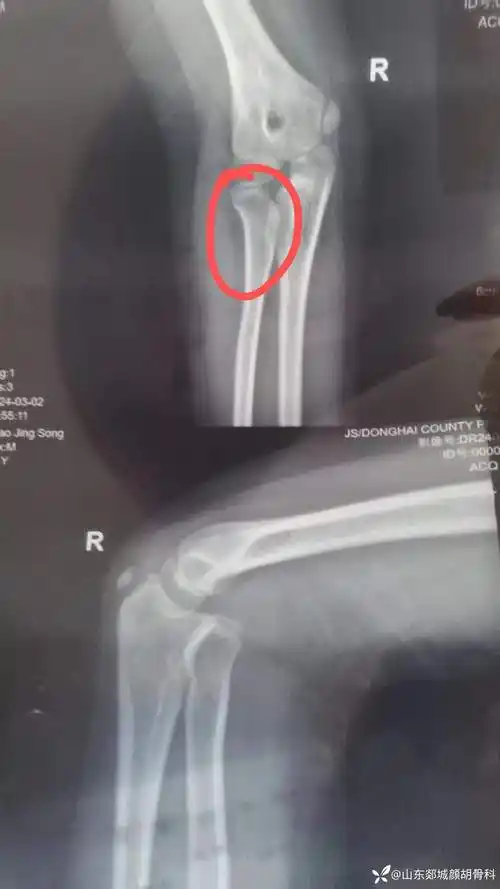

右桡骨小头脱位是先天性的还是外伤后引发